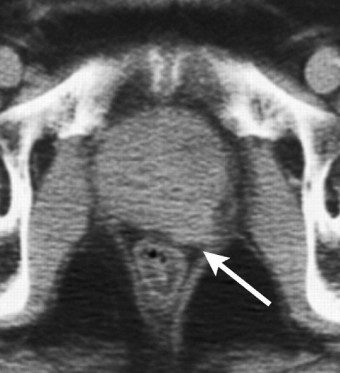

- 영상 검사: 초음파, MRI, CT 스캔 등을 통해 전립선의 상태와 암의 퍼진 정도를 확인합니다.